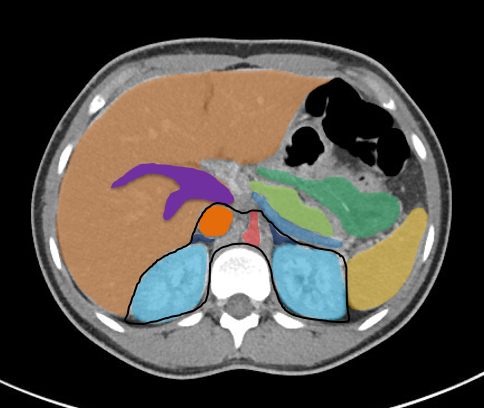

Bildergalerie (5 Bilder)

1 (Bild 1 von 5) Vorwärts »

« Zurück 5 (Bild 5 von 5)